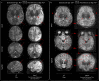

Findings: Between September 23, 2021 and October 25, 2022, 102 paired scans were acquired in 87 infants; 1.17 paired scans per infant. Median age 9 days, median postmenstrual age 40+2 weeks (range: 31+3-53+4). Infants had a range of intensive care requirements. No adverse events observed. Optimised ULF sequences can visualise key neuroanatomy and brain abnormalities. In finalised neonatal sequences: T2w imaging distinguished grey and white matter (7/7 infants), ventricles (7/7), pituitary tissue (5/7), corpus callosum (7/7) and optic nerves (7/7). Signal congruence was seen within the posterior limb of the internal capsule in 10/11 infants on finalised T1w scans. In addition, brain abnormalities visualised on ULF optimised sequences have similar MR signal patterns to 3T imaging, including injury secondary to infarction (6/6 infants on T2w scans), hypoxia-ischaemia (abnormal signal in basal ganglia, thalami and white matter 2/2 infants on T2w scans, cortical highlighting 1/1 infant on T1w scan), and congenital malformations: polymicrogyria 3/3, absent corpus callosum 2/2, and vermian hypoplasia 3/3 infants on T2w scans. Sequences are susceptible to motion corruption, noise, and ULF artefact. Non-identified pathologies were small or subtle.